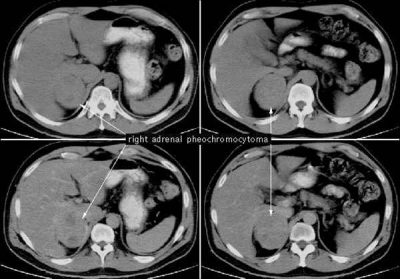

- טומוגרפיה ממוחשבת - בדיקה המאפשרת הדגמה טובה של יותרת-הכליה והשאת, והיא בדיקת הבחירה להדגמת יותרת-הכליה. חסרונה הוא בכך שהיא מדגימה גושים הגדולים מ- 1 ס"מ ואינה יכולה להבחין בין שאת פעילה לזו שאינה פעילה (תמונה 6.14- 7).